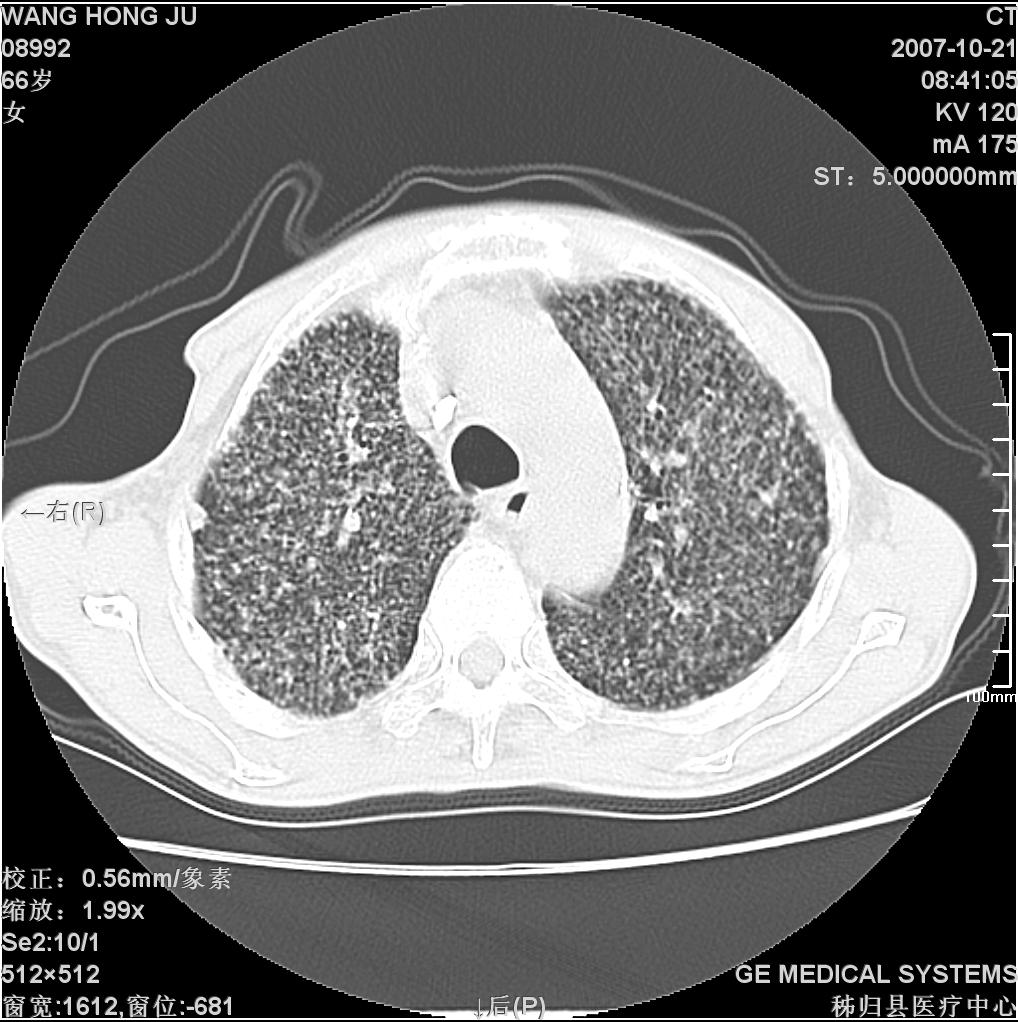

患者咳嗽月余,高热数天,咳黄色稍脓痰。

高热数天,咳黄色稍脓痰,肯定应该有急性化脓性感染,左上叶舌段及右肿叶可见多量斑片状及支气管气像,首先考虑肺部感染合并血型播散性肺脓肿(脓肿为早期改变),其次不排除有肺泡癌,第三不排除结核,建议治疗后复查

双肺野分布多个小结节状高密度影,其内散在斑片状模糊影,气管。支气管通畅,纵隔内淋巴结钙化,胸膜局限性增厚粘连,胸腔少量积液。结合病史考虑结核并感染的可能性大,胸膜炎并积液。肺泡癌待排。

首先考虑肺部感染合并血型播散性肺脓肿(脓肿为早期改变),其次考虑亚急性血行播散型肺tb.

纵隔内见钙化的淋巴节,上肺见钙化灶,双肺均匀弥漫分布小结节影,边缘较清楚,能不能考虑是在矽肺的基础上并发的结核和感染,请详细了解病史结合临床.